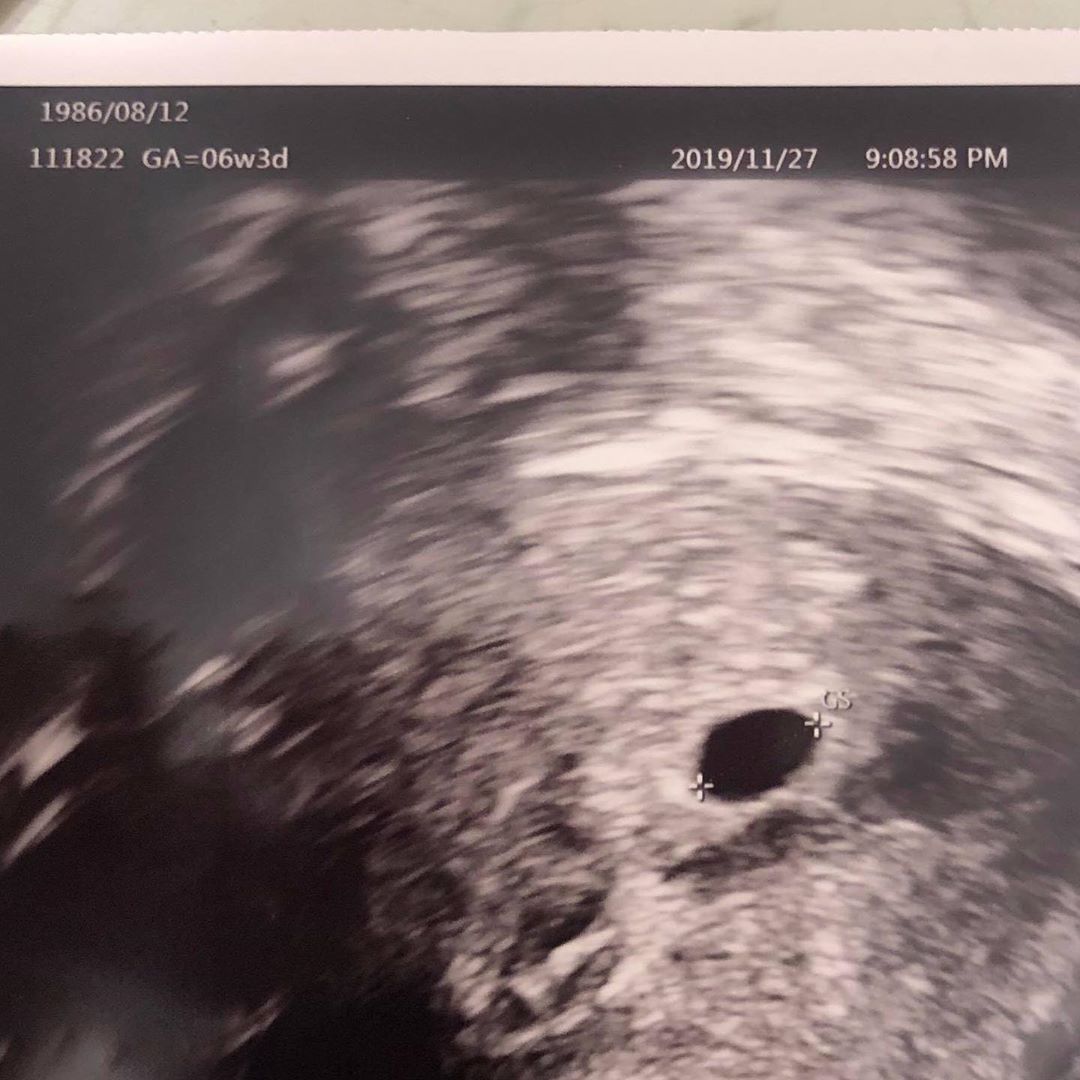

Keanna在6日深夜突然在IG發文貼出一張「超音波照」,讓大家都驚呼不已,我們從照片中可以看到,這張超音波是在2019年11月27日拍的,當時胎兒已經6週又3天大了,以時間來推算的話,到今天也差不多有8週了!雖然扣嫂在貼文中沒有多說什麼,不過超音波照左上角寫著「1986/08/12」,正好就是她本人的生日,讓大家都更加確定這就是她的超音波照!